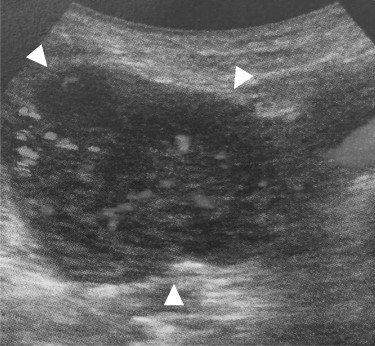

A 69-year-old woman presented to our institution with right abdominal pain. There was nothing special to mention in her family history. Her past medical history included horseshoe kidney, gastric ulcer, and asthma. Physical examination revealed a slight tenderness of the right quadrant abdomen. All laboratory parameters including the tumor markers carcinoembryonic antigen and carbohydrate antigen 19-9 were within normal limits. Abdominal ultrasonography showed a regularly shaped uniform tumor of about 50 mm in diameter that was located in the right retroperitoneum ventral to the right part of the horseshoe kidney. The tumor was hypervascularized (Fig. 1). Computed tomography (CT) showed a tumor of 80 mm in diameter ventral to the right part of the horseshoe kidney and the dorsal side of the descending part of the duodenum. On contrast-enhanced CT, the tumor showed late-phase enhancement. There were no findings of invasion into any organs and right ovarian vein ran through the tumor (Fig. 2). No metastases to organs or swollen lymph nodes were found. Magnetic resonance imaging (MRI) showed a tumor that was isointense with respect to muscle on T1-weighted images and of high-signal intensity on T2-weighted images (Fig. 3). No fatty components were detected in the tumor. Endoscopic ultrasonography showed a regularly shaped and hypoechoic tumor with no connection to the right part of the horseshoe kidney or duodenum (Fig. 4). Our working diagnosis was a retroperitoneal tumor that could be either a malignant lymphoma, leiomyoma or gastrointestinal stromal tumor.

Abdominal ultrasonography: the tumor located lateral side of the right kidney, 40 mm in diameter (arrowhead). The tumor had much blood flow.